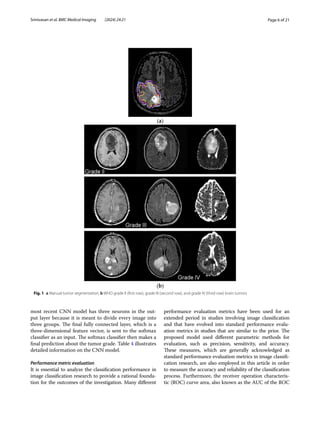

Fig. 1 a Manual tumor segmentation; b WHO grade II (first row), grade III (second row), and grade IV (third row) brain tumors

tumors (931 slices). Figure 1 depicts the different grades

of brain tumors from the dataset. Totally, 3165 images